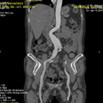

Aorta Abd VR

腹主动脉瘤的局部图像,显示其整体形态

Aneurysm Measurements

Proximal neck: 59.8 mm

Neck angulations: 98˚ 133.3°

Diameters of aneurysm ( @ max area) :

Dmax =42.2 mm Dmin =38.1 mm

Volume of aneurysm 125.769 cm3

Diameters of Aorta

Diameters of aorta within pararenal segment (mm):

Inf RA Level: Dmax = 20.2 Dmin = 17.9

Diameters of aorta 5, 10, 15mm below Inf RA (mm):

Dmax = 19.8 Dmin = 17.9

Dmax = 18.8 Dmin = 16.8

Dmax = 19.7 Dmin = 18.1

Diameter of aorta at aortic bifurcation:

Dmax = 44.2 Dmin = 39.3

Diameter of Iliac & Femoral Arteries

Diameters of left/right common iliac artery at its bifurcation (mm):

R Iliac Bif: Dmax = 26.4 Dmin =17.1

R Femoral: Dmax =13.6 Dmin =11.1

L Iliac Bif: Dmax = 23.2 Dmin = 20.1

L Femoral: Dmax = 11.8 Dmin = 8.7

Diameters of Abdominal Branches

Diameters of major abdominal branches (mm) :

Celiac: Dmax = 9.2 Dmin = 8.6

SMA: Dmax = 11.3 Dmin =10.1

L RA: Dmax = 9.0 Dmin = 8.7

R RA: Dmax = 6.6 Dmin = 6.1

Distances

Useful distances (mm):

Inf RA--AAA 61.0, Inf RA—Aorta Bif 157.7, Aorta Bif –L Iliac Bif 21.5 Aorta Bif –R Iliac Bif 40.8,

Orientation of Branch Vessels

Showing orientation of branch vessels for fenestrated device:

Celiac 1:00 O'Clock, SMA 12:00, R RA 9:00, L RA 3:30